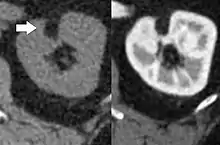

| Angiomyolipoma in both kidneys (arrows) in computer tomography. The tumours are hypodense (dark) due to fat content | |

Three methods of scanning can detect Angiomyolipomas: ultrasound, computed tomography (CT), and magnetic resonance imaging (MRI).[5] Ultrasound is standard and is particularly sensitive to the fat in Angiomyolipomas, but less so to the solid components. However, accurate measurements are hard to make with ultrasound, particularly if the Angiomyolipoma is near the surface of the kidney (grade III).[4] CT is very detailed and fast, and allows accurate measurement. However, it exposes the patient to radiation and the dangers that a contrast dye used to aid the scanning may itself harm the kidneys. MRI is safer than CT, but many patients (particularly those with the learning difficulties or behavioural problems found in tuberous sclerosis) require sedation or general anaesthesia, and the scan cannot be performed quickly.[3] Some other kidney tumours contain fat, so the presence of fat is not diagnostic. Distinguishing a fat-poor angiomyolipoma from a renal cell carcinoma (RCC) can be difficult.[6] Both minimal fat AMLs and 80% of the clear-cell type of RCCs display signal drop on an out-of-phase MRI sequence compared to in-phase.[7] Thus, a lesion growing at greater than 5 mm per year may warrant a biopsy for diagnosis.[3]